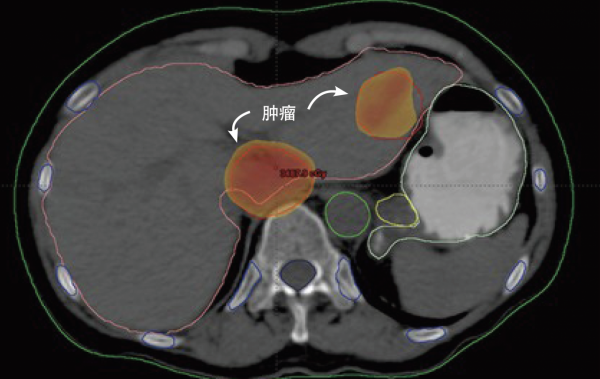

經過簡單的問診,醫生清楚了她的症狀:陰道深處觸痛、出血。在檢查室,醫生髮現他的子宮中長了一個腫塊,疼痛和出血就是來源於此。

於是醫生從腫塊上取下了樣本,告訴拉克斯需要進行細胞學檢查才能做出診斷,讓她回家等待檢查結果。

然而,在手術之前,在並未告知患者的情況下,醫生先用手術刀在拉克斯的腫瘤塊上,切下了兩小片組織,並儲存了下來。